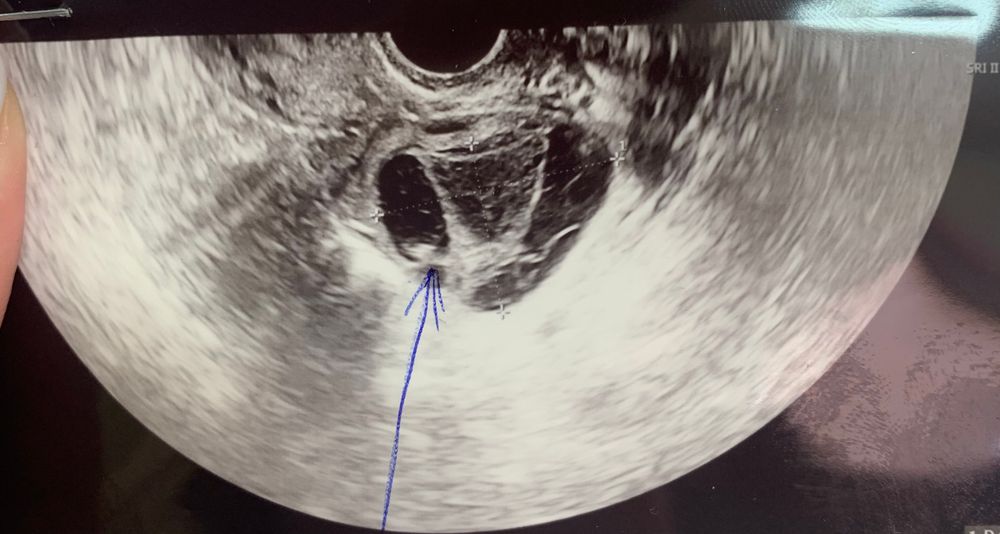

Киста желтого тела

Всем привет, пошла на узи после задержки в 6 дней, обычно после дюфа всегда М приходят как по часам, а тут задержка, в начале цикла стимулировалась летрозолом, но сказали, что ничего не выросла и я начала пить дюф, чтобы начать новый цикл, с задержкой побежала на узи, там непонятно, вроде как 2 желтый тела и овуляция возможно случилась поздняя, но я же пила дюф, и фолики были маленькие, и жидкость есть в позадиматочном, не знаю теперь что и думать, надеюсь на лучшее, посмотрим через недельку